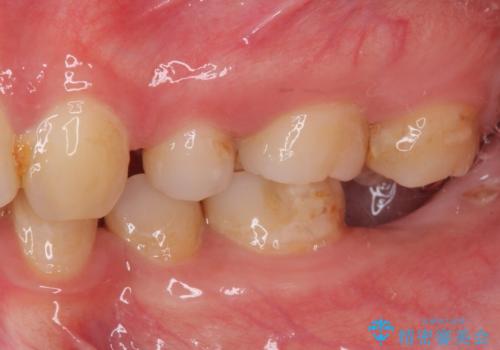

- 左下欠損部のインプラント治療と、右下の歯の痛みを気にして来院された患者様です。

左下の欠損部は、世界中で高い信頼を得ているストローマンインプラントを用いて治療を行うこととしました。

ただし、長期間欠損を放置していたことで、咬み合う上の奥歯が動いてしまっていたので、まずは上顎奥歯の部分矯正を行い、より理想的な咬み合わせを目指すこととしました。

右下の歯は、レントゲン上歯髄組織まで虫歯が及んでいるように見えましたが、痛みの症状は強くなかったため、歯髄組織の一部を断ち歯根部分の組織を保存する生活歯髄療法を第一選択に処置を進めて行くこととしました。

まず生活歯髄療法を行い、その後部分矯正やインプラント処置を行いましたが、最初の処置から1年以上経っても右下奥の処置歯の神経組織に異常は認められませんでした。

部分矯正を行ったことで、違和感のない咬み合わせを達成することができました。